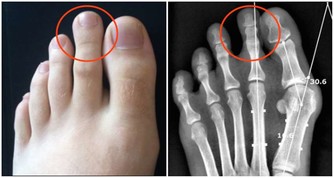

莧菜平衡酸鹼值,補血又使痛風消。莧菜有紅莧、白莧,應該大量推廣。

尿酸痛風的人,可以每天吃一碗莧菜湯,或像我們客家人用莧菜煮麵線,但是不要放吻仔魚。

莧菜能平衡酸鹼,你的尿酸痛風就會好。

不要吃冰的東西,不要吃香蕉,香蕉吃了痛風就發作,因為裡面有鉀離子。

莧菜補血,就是紅莧菜,又使痛風消,

所以每天用一碗面線、一把莧菜,保證不會體重增加,保證尿酸痛風全部消掉。